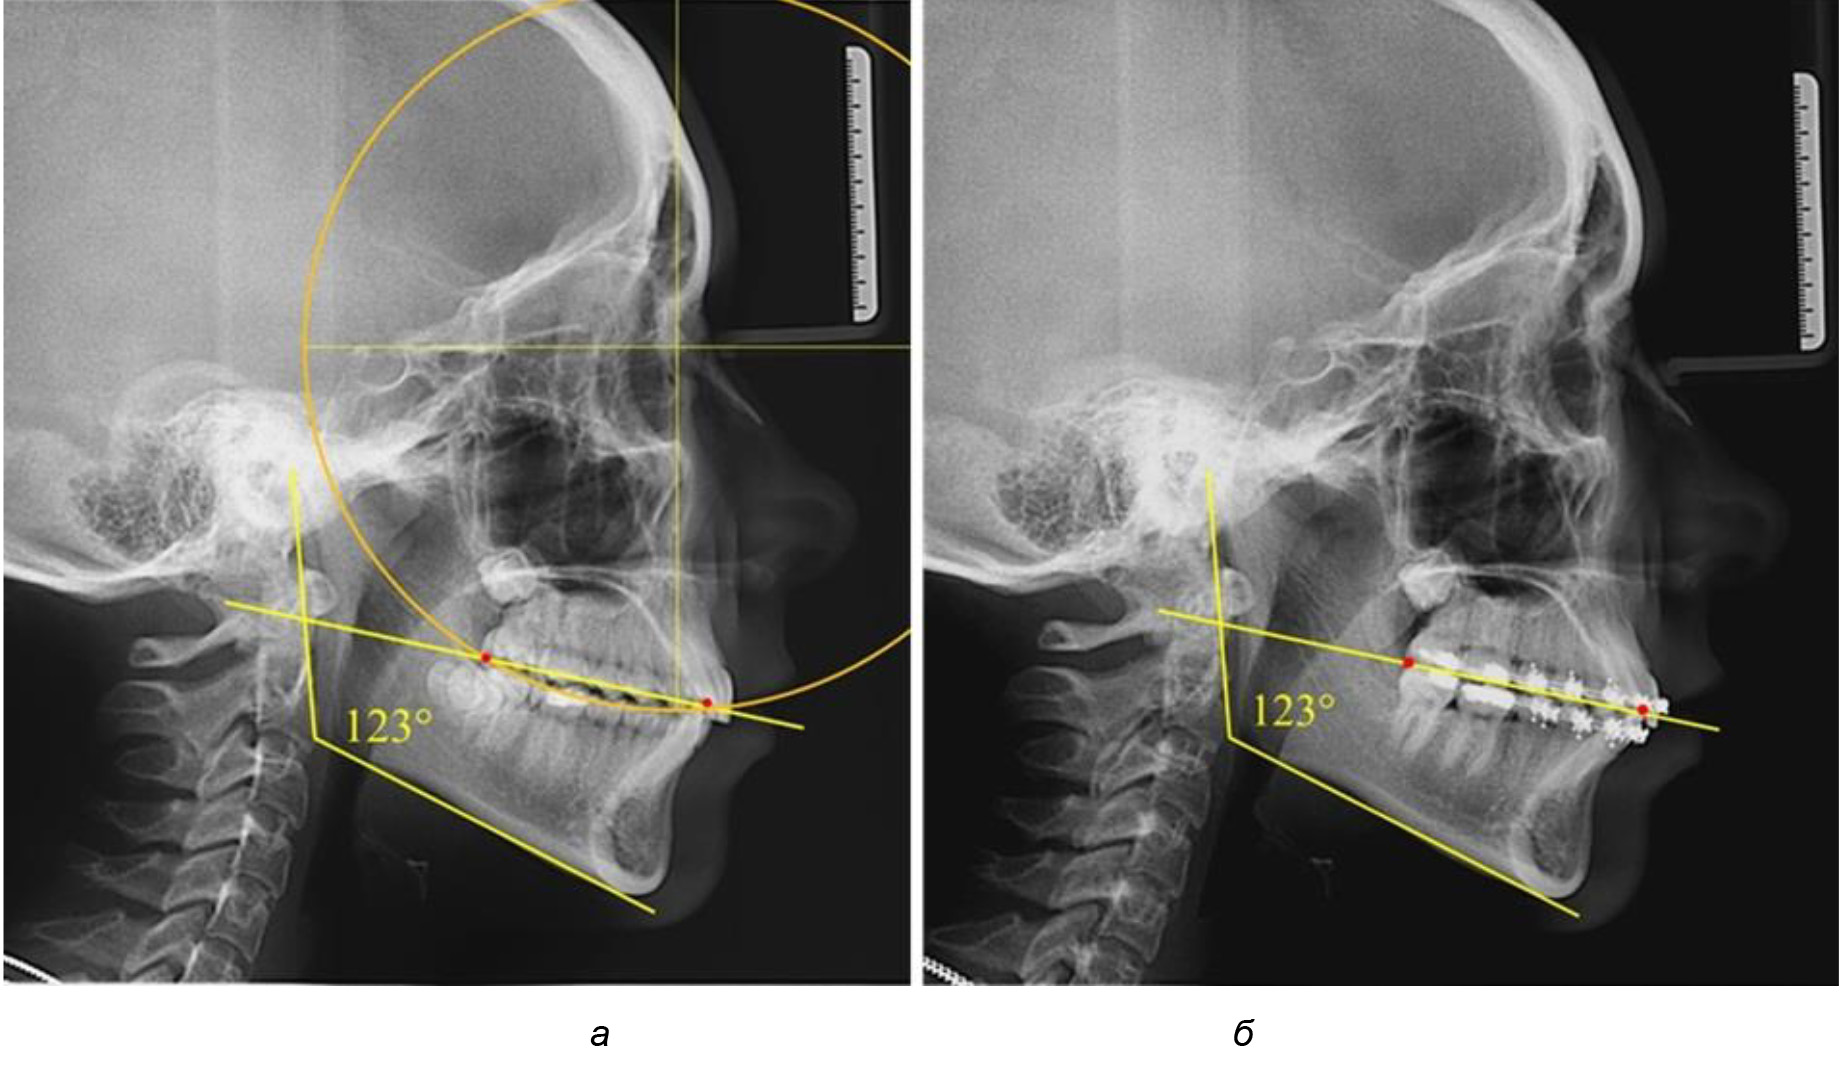

В ходе исследования установлено, что в 1-й подгруппу вошли ТРГ и ОПТГ 18 человек 1-й группы, что составило (29,03 ± 5,78) % от всех пациентов, рентгенограммы которых были проанализированы. У всех пациентов величина угла нижней челюсти была более 125° и в среднем составила (129,89 ± 3,62)° и характеризовала вертикальный тип нижней челюсти.

Учитывая существенную вариабельность линейных показателей, обусловленных типологическими (гнатическими и дентальными) вариантами зубочелюстных дуг, анализ проводили только при измерении глубины кривой Spee в наиболее углубленном месте и оценивали относительный показатель через отношение радиуса круга к сагиттальному расстоянию окклюзионной линии.

Анализ результатов показал, что глубина кривой Spee в среднем по подгруппе составил (4,12 ± 0,53) мм как при анализе ТРГ, так и ОПТГ.

Деление величины радиуса круга к длине окклюзионной линии составило 1,623 ± 0,02. Таким образом, для определения радиуса окружности, соответствующей кривизне окклюзионного контура боковой ТРГ, необходимо измерить расстояние между передней и задней окклюзионными точками и последующим умножением полученной величины на число Фибоначчи (рис. 2).

Рис. 2. Особенности кривой Spee на ТРГ (а) и ОПТГ (б) у людей с признаками вертикального роста